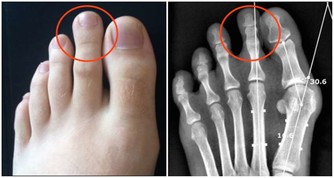

1、關節疼痛、紅腫

大量尿酸結晶沉積關節腔內,可誘發痛風性關節炎。患者往往在深夜突然出現關節疼痛,如刀割般疼痛,嚴重時會影響走路,伴關節紅腫,局部皮膚溫度升高的症狀。

首次發作以第一蹠趾關節(大腳趾與腳掌連接的關節)最常見,佔90%左右,踝關節、膝關節、腕關節、指間關節等也會受累。

2、痛風石

如果尿酸控制不好,痛風反復發作,大量尿酸結晶沉積在皮下、關節腔內,會形成痛風石,造成關節骨質破壞、畸形。一旦出現痛風石,體內尿酸已經非常高了。